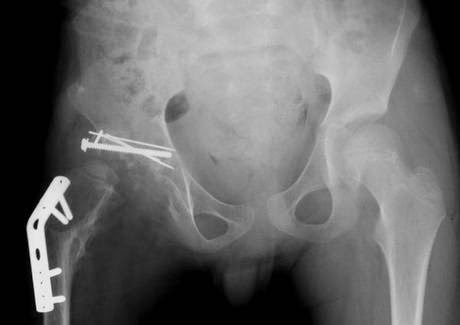

Ο Wengshoel πήρε το μέρος του σώματος στο σπίτι έπειτα από χειρουργική επέμβαση αντικατάστασης ισχίου, και αφού το έβαλε στην κατσαρόλα προκειμένου να βράσει, το κατανάλωσε με πατάτες ογκρατέν και ένα ποτήρι κρασί.

Ο Wengshoel, που γεννήθηκε με παραμορφωμένο ισχίο και υπέστη σε πολλές αποτυχημένες επιχειρήσεις κατά την παιδική ηλικία, είχε περάσει το μεγαλύτερο μέρος της ζωής του σε μια αναπηρική καρέκλα ή με πατερίτσες πριν η ζωή του αλλάξει με υποστεί στη χειρουργική επέμβαση που του άλλαξε τη ζωή, σε ηλικία 21 ετών.